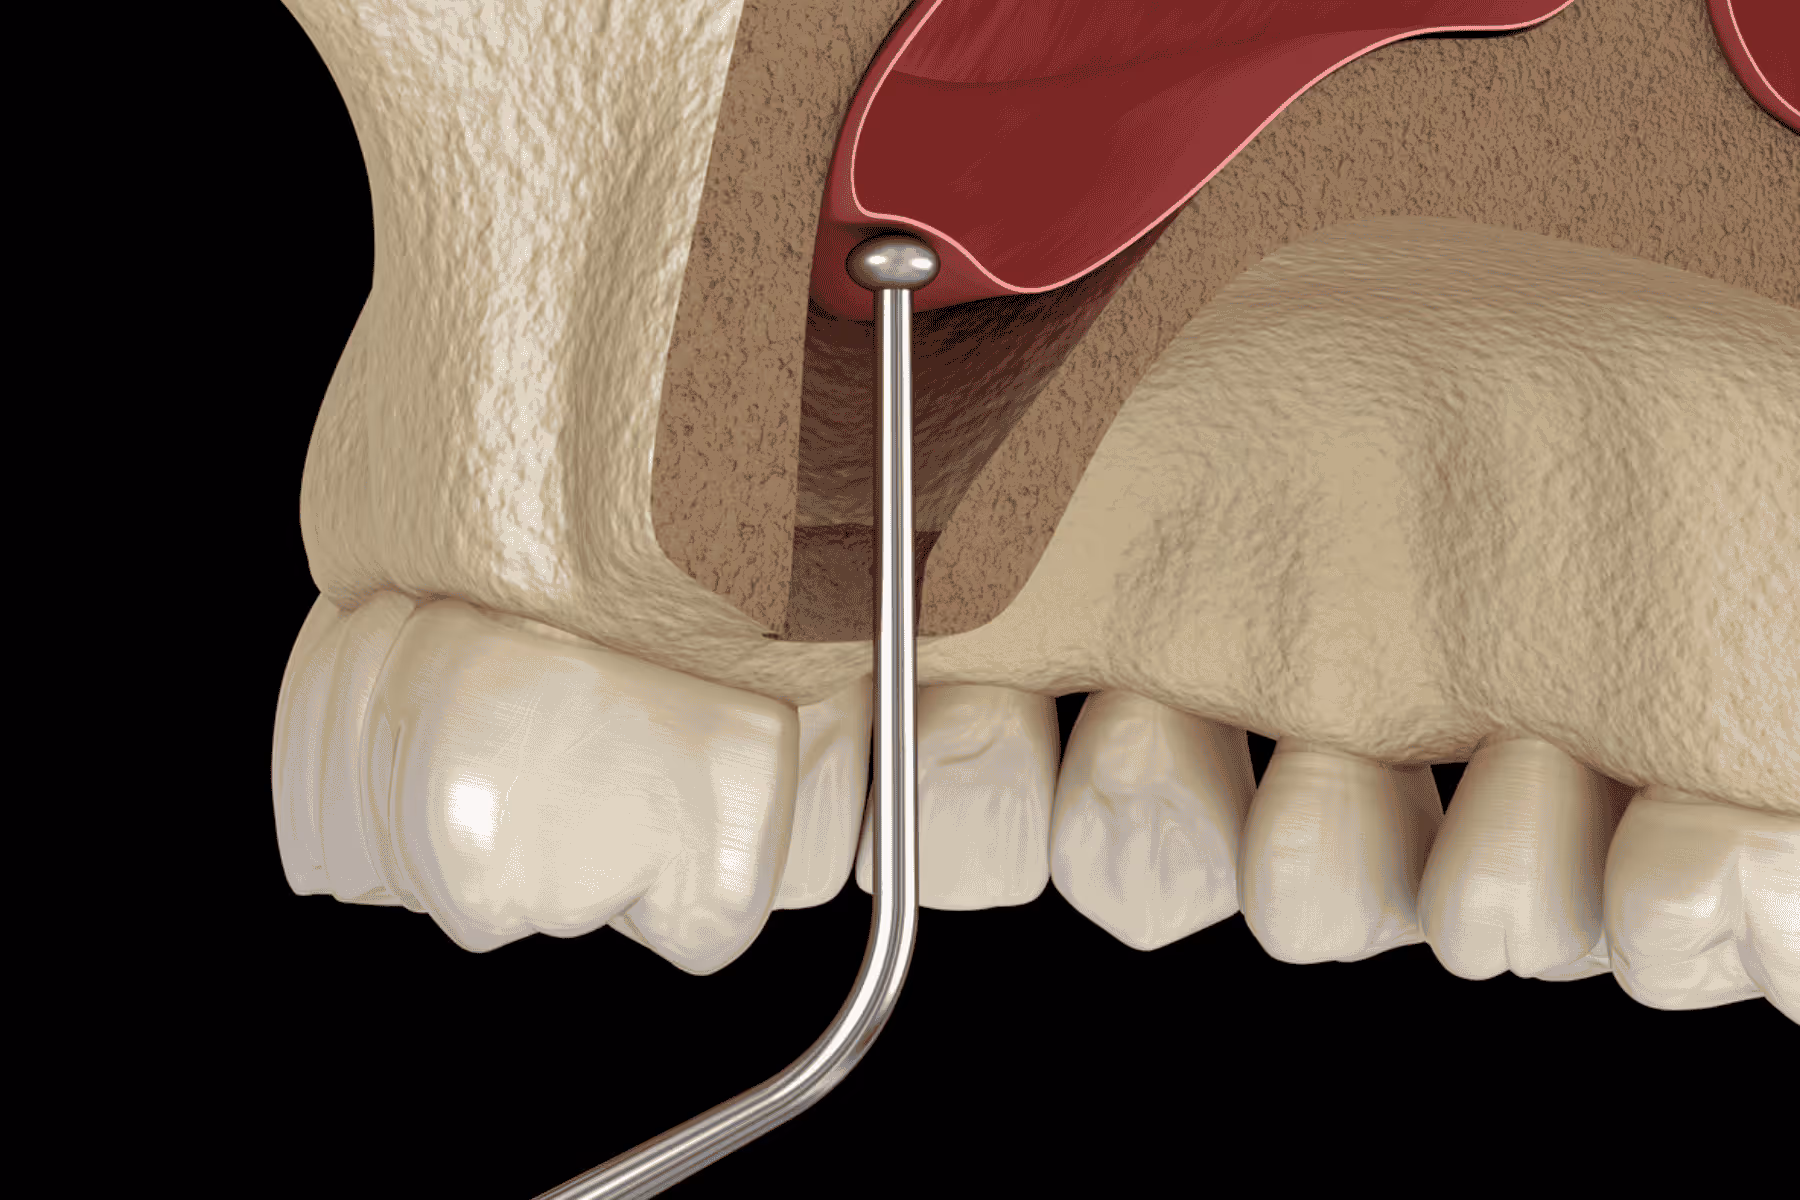

You might not know that anatomy will vary from person to person, so CBCT scanning is essential before implant surgery.Every patient’s anatomy is genuinely unique, with nerve pathways, sinus cavities and even bone structures varying in size, position and shape - so believe it when we say no two cases are the same, hence, why pre-implant planning and consultations with a dentist are so detailed and paramount to treatment.CBCT scans, in this instance, help us understand your unique oral anatomy and how the surgery will play out for you. For example, your inferior alveolar nerve, which runs along the lower jaws, might be higher or lower, or your maxillary sinus in the upper jaws extend further than expected, impacting the locations where your implant can be safely placed.All of these considerations are made in the initial stages, contributing to the dental implant’s overall incredible success rate of 98%.

Without taking a CBCT scan before treatment, there’s a higher risk that the dental implant is positioned too close to or, worse, in contact with a nerve, leading to temporary or even permanent numbness. In the upper jaws, there is an increased risk of the dental implant being placed near the sinus cavity, causing complications and implant failure.